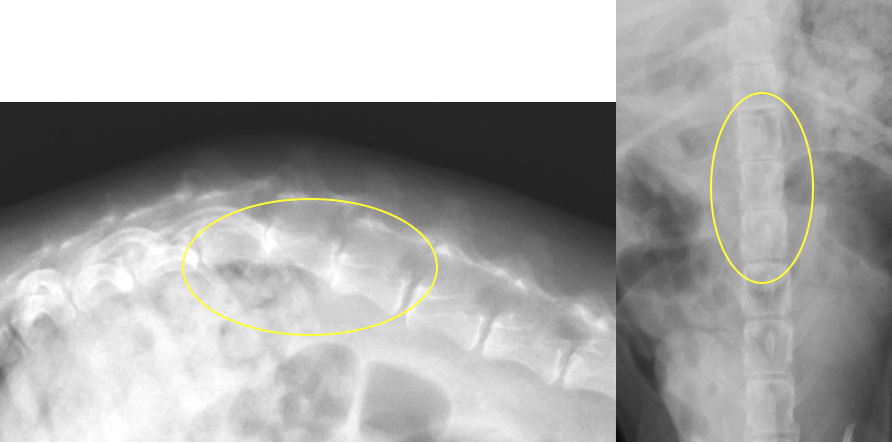

椎体骨折・椎体不安定に対する椎体固定術

交通事故などで背骨が折れてしまったり、椎間板の問題でズレが生じ不安定性がある場合、背骨の中を通る脊髄に障害をきたし、歩行異常や麻痺などの症状が出ます。また、大きな血管を損傷し、死に至る場合もあります。椎体骨折や椎体不安定の場合、椎体を何らかの方法で固定し、元の位置に安定化させる必要があります。小型犬〜中型犬で安全性が高く強固な固定は、折れている(ずれている)背骨とその前後の椎体にスクリューを打ち込み、打ち込んだスクリューを骨セメント(PMMA)という物質で固める方法です。他にもプレートやピンを使用する方法もあります。 手術自体は難易度が高いのですが、Cアームという透視装置を導入したことで以前ほどの危険性はなくなりました。

椎間板の問題で椎体にずれが生じた症例です。骨折ほど大きなズレではないため、片側からスクリューを打ち込み、それを骨セメントで固定しています。この症例は椎間板ヘルニアの手術で減圧術(ヘミラミネクトミー)も同時に行いました。術後の経過はよく、うまく歩けなかったのが、通常通り歩けるようにまでなりました。